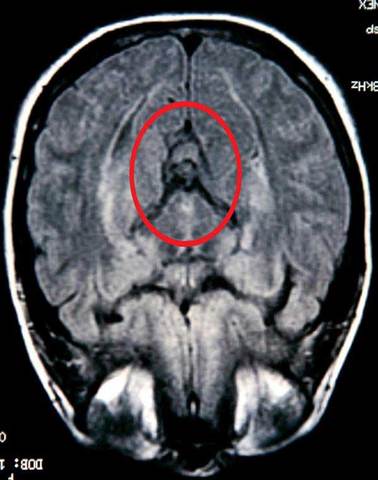

• Amnesia

Amnesia

Amnesia mean lossing some or all you're memory. You can get Amnesia with a bump on the head or a disease. No matter how you get it you have the same affects. Of couse you'll lose you're memory. Sometimes it last for days, weeks, years or maybe all you're life. When having Amnesia you can't remember the past or new events coming up.